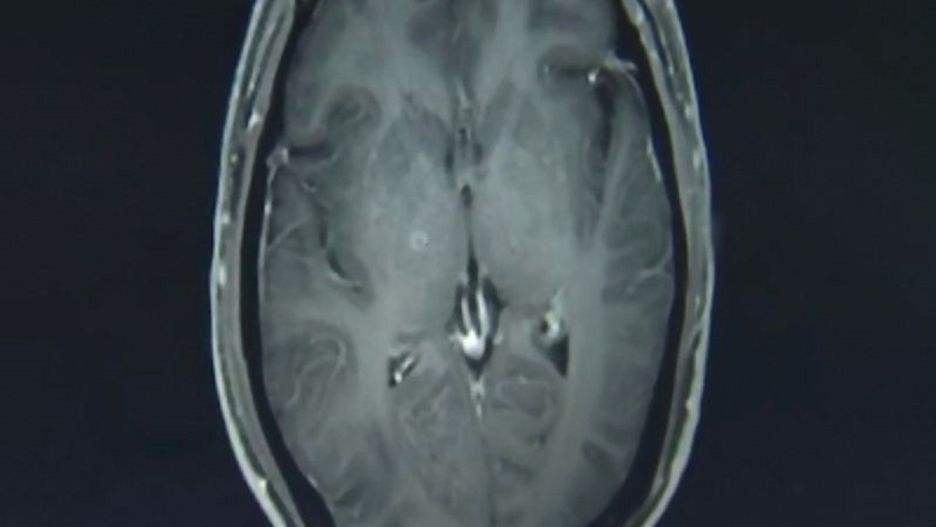

Niedogotowane mięso przyczyną koszmarnych dolegliwości u mężczyzny, który je zjadł. Kiedy zgłosił się do lekarzy, skarżył się na tak wiele dolegliwości, że medycy nie wiedzieli, od czego zacząć. Dokładne badanie wykazało setki tasiemców w mózgu i klatce piersiowej mężczyzny.

43-letni mężczyzna z Chin zgłosił się do szpitala z szeregiem różnych dolegliwości. Od kilku tygodni cierpiał na silne bóle głowy, nudności. Kilka razy stracił przytomność, miał także napady padaczkowe.

Lekarze przeprowadzili szereg badań mózgu. Wyniki ujawniły uszkodzenia spowodowane obecnością larw tasiemca.

Zhu Zhong-fa został objęty opieką oddziału chorób zakaźnych. Dodatkowe skany ujawniły jeszcze więcej pasożytów w innych częściach ciała. Najwięcej było ich w klatce piersiowej. Łącznie mężczyzna miał w sobie ponad 700 larw tasiemca.